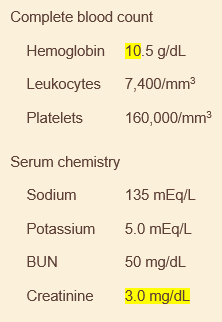

70M here for fatigue. hasnt seen a doctor in 20 years. eats lots of fast food and takes otc pain meds for intermittent back pain. urinalysis with trace protein, no casts. s4 and strong apical impulse on exam. US of abdomen reveals bilateral small kidneys

hypertensive nephrosclerosis